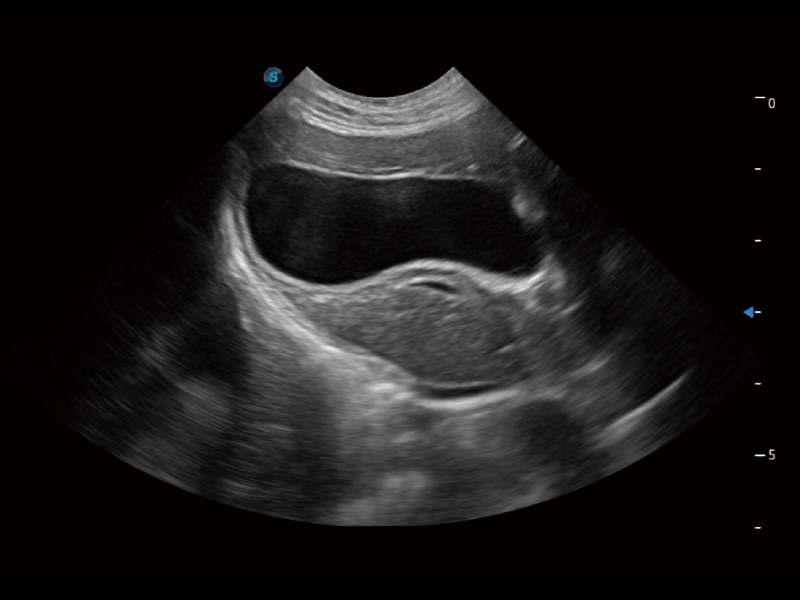

大型犬、马科、农场动物及大型异宠动物

一键自动识别膀胱壁及自动测量膀胱容积,不受膀胱形状和大小的限制,帮助医生快速精准获得测量的数据。

ProPet 70专为动物医生设计,对不同的动物体型和生理结构作出了针对性的优化。通过动物影像专用软件,可满足个性化的应用需求,帮助动物医生获得更精确的诊断数据。

ProPet 70 全新的动物超声智能软件和丰富的探头群,为动物医生提供了高清晰度和精细分辨率的图像,无论在宠物、马科、畜牧还是实验室动物等应用中都可以轻松应对,为您的日常工作带来满意的体验。